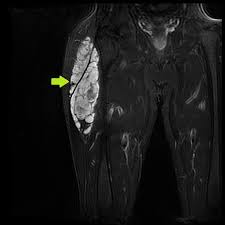

Extraskeletal myxoid chondrosarcoma (EMC) is a scarce soft, fleshy muscle or tissue tumor of complex molecular and ultra-architectural characteristics. This kind of sarcoma prognosis is not easy, like other soft tissue sarcomas diagnosed by clinical and radiological findings. This sarcoma has a unique gene fusion (EWSR1-NR4A3) that helps build a differential diagnosis. The reported cases showed that most EMCs appeared in the thigh position, affecting the deep tissues of limb girdles and proximal extremities. Whereas less common occurrences include the head, trunk, neck, pelvis, abdomen, paraspinal soft tissue, and foot, while it rarely occurs in the retroperitoneum, skull, pleura, and bone.

Extraskeletal myxoid chondrosarcoma, also called EMC, is an uncommon, low-grade cancerous type that grows in soft tissues outside the bone and usually has certain changes in the NR4A3 gene that result in special fusion proteins to be made. They are a type of soft tissue tumor. This diagnostic usually occurs in the thigh but may also occur in the knee, buttock, or trunk (chest and abdomen). They may grow large and expand to nearby tissues or other parts of the body, particularly the lungs. It is usually developed in the deep parts of proximal extremities and limb girdles and occurs more frequently in men than women. They may also reappear many years after the treatment. Extraskeletal myxoid chondrosarcomas usually occur in middle-aged or older adults and are rarely seen in minors and youngsters.